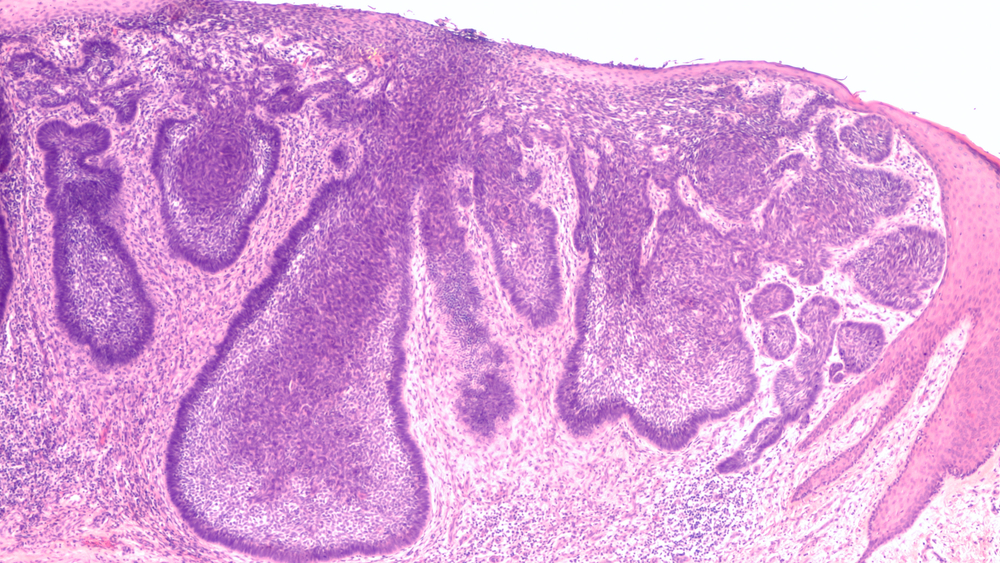

The diagnosis of basal cell carcinoma begins with a thorough skin examination by a dermatologist at Golden State Dermatology. During this exam, your provider will carefully inspect any suspicious lesions and may use a dermatoscope, a specialized magnifying device, to get a closer look at the skin’s surface.

If a suspicious lesion is identified, your dermatologist will perform a skin biopsy to confirm the diagnosis. This involves removing a small sample of tissue for examination under a microscope, which can definitively determine whether cancer cells are present and what type of skin cancer it is.